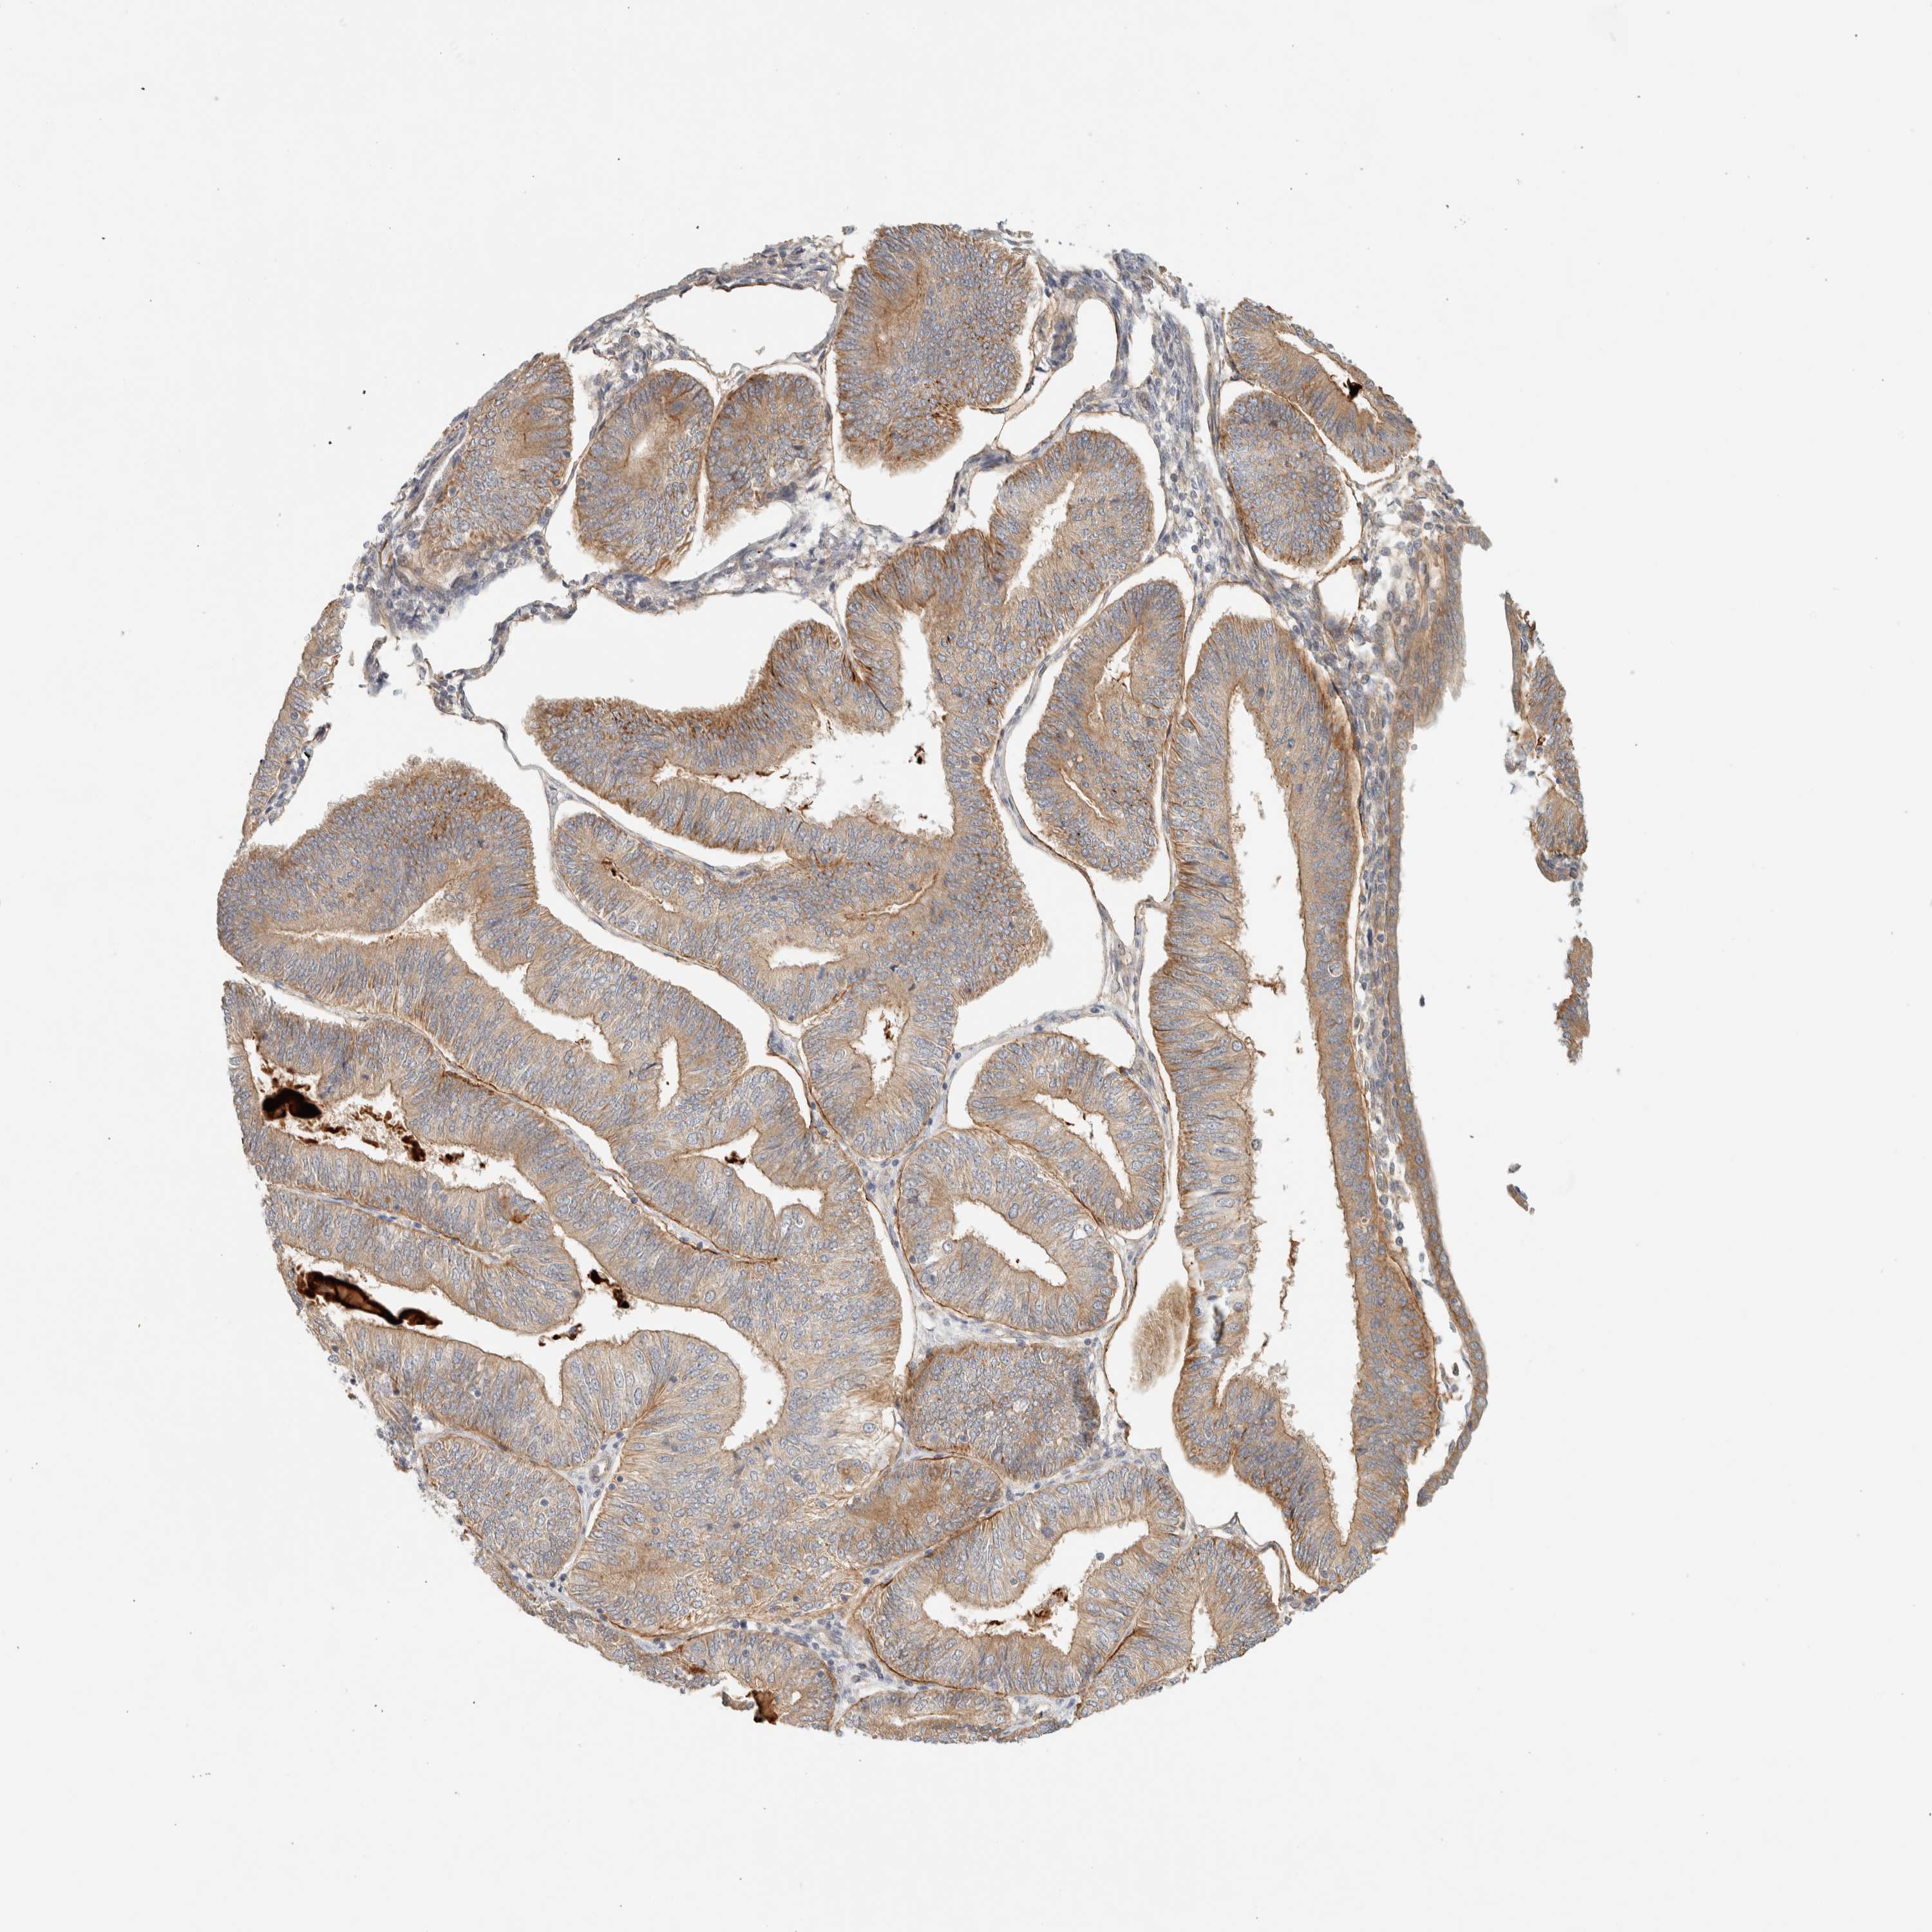

ENDOMETRIAL CANCER - Protein expressioni

A mouse-over function shows sample information and annotation data. Click on an image to view it in a full screen mode. Samples can be filtered based on level of antibody staining by selecting one or several of the following categories: high, medium, low and not detected. The assay and annotation is described here.

Note that samples used for immunohistochemistry by the Human Protein Atlas do not correspond to samples in the TCGA dataset.

Antibody stainingi

Antibody staining in the annotated cell types in the current human tissue is reported as not detected, low, medium, or high, based on conventional immunohistochemistry profiling in selected tissues. This score is based on the combination of the staining intensity and fraction of stained cells.

Each image is clickable and will lead to virtual microscopy that enables deeper exploration of all samples and also displays staining intensity scores, fraction scores and subcellular localization as well as patient and tissue information for each sample.

Antibody HPA001869

Antibody HPA023882

Staining

High

Medium

Low

Not detected

Intensity

Strong

Moderate

Weak

Negative

Quantity

>75%

75%-25%

<25%

None

Location

Nuclear

Cytoplasmic/membranous

Cytoplasmic/membranous,nuclear

Adenocarcinoma, NOS

Neoplasm, malignant, NOS

Adenoma, NOS